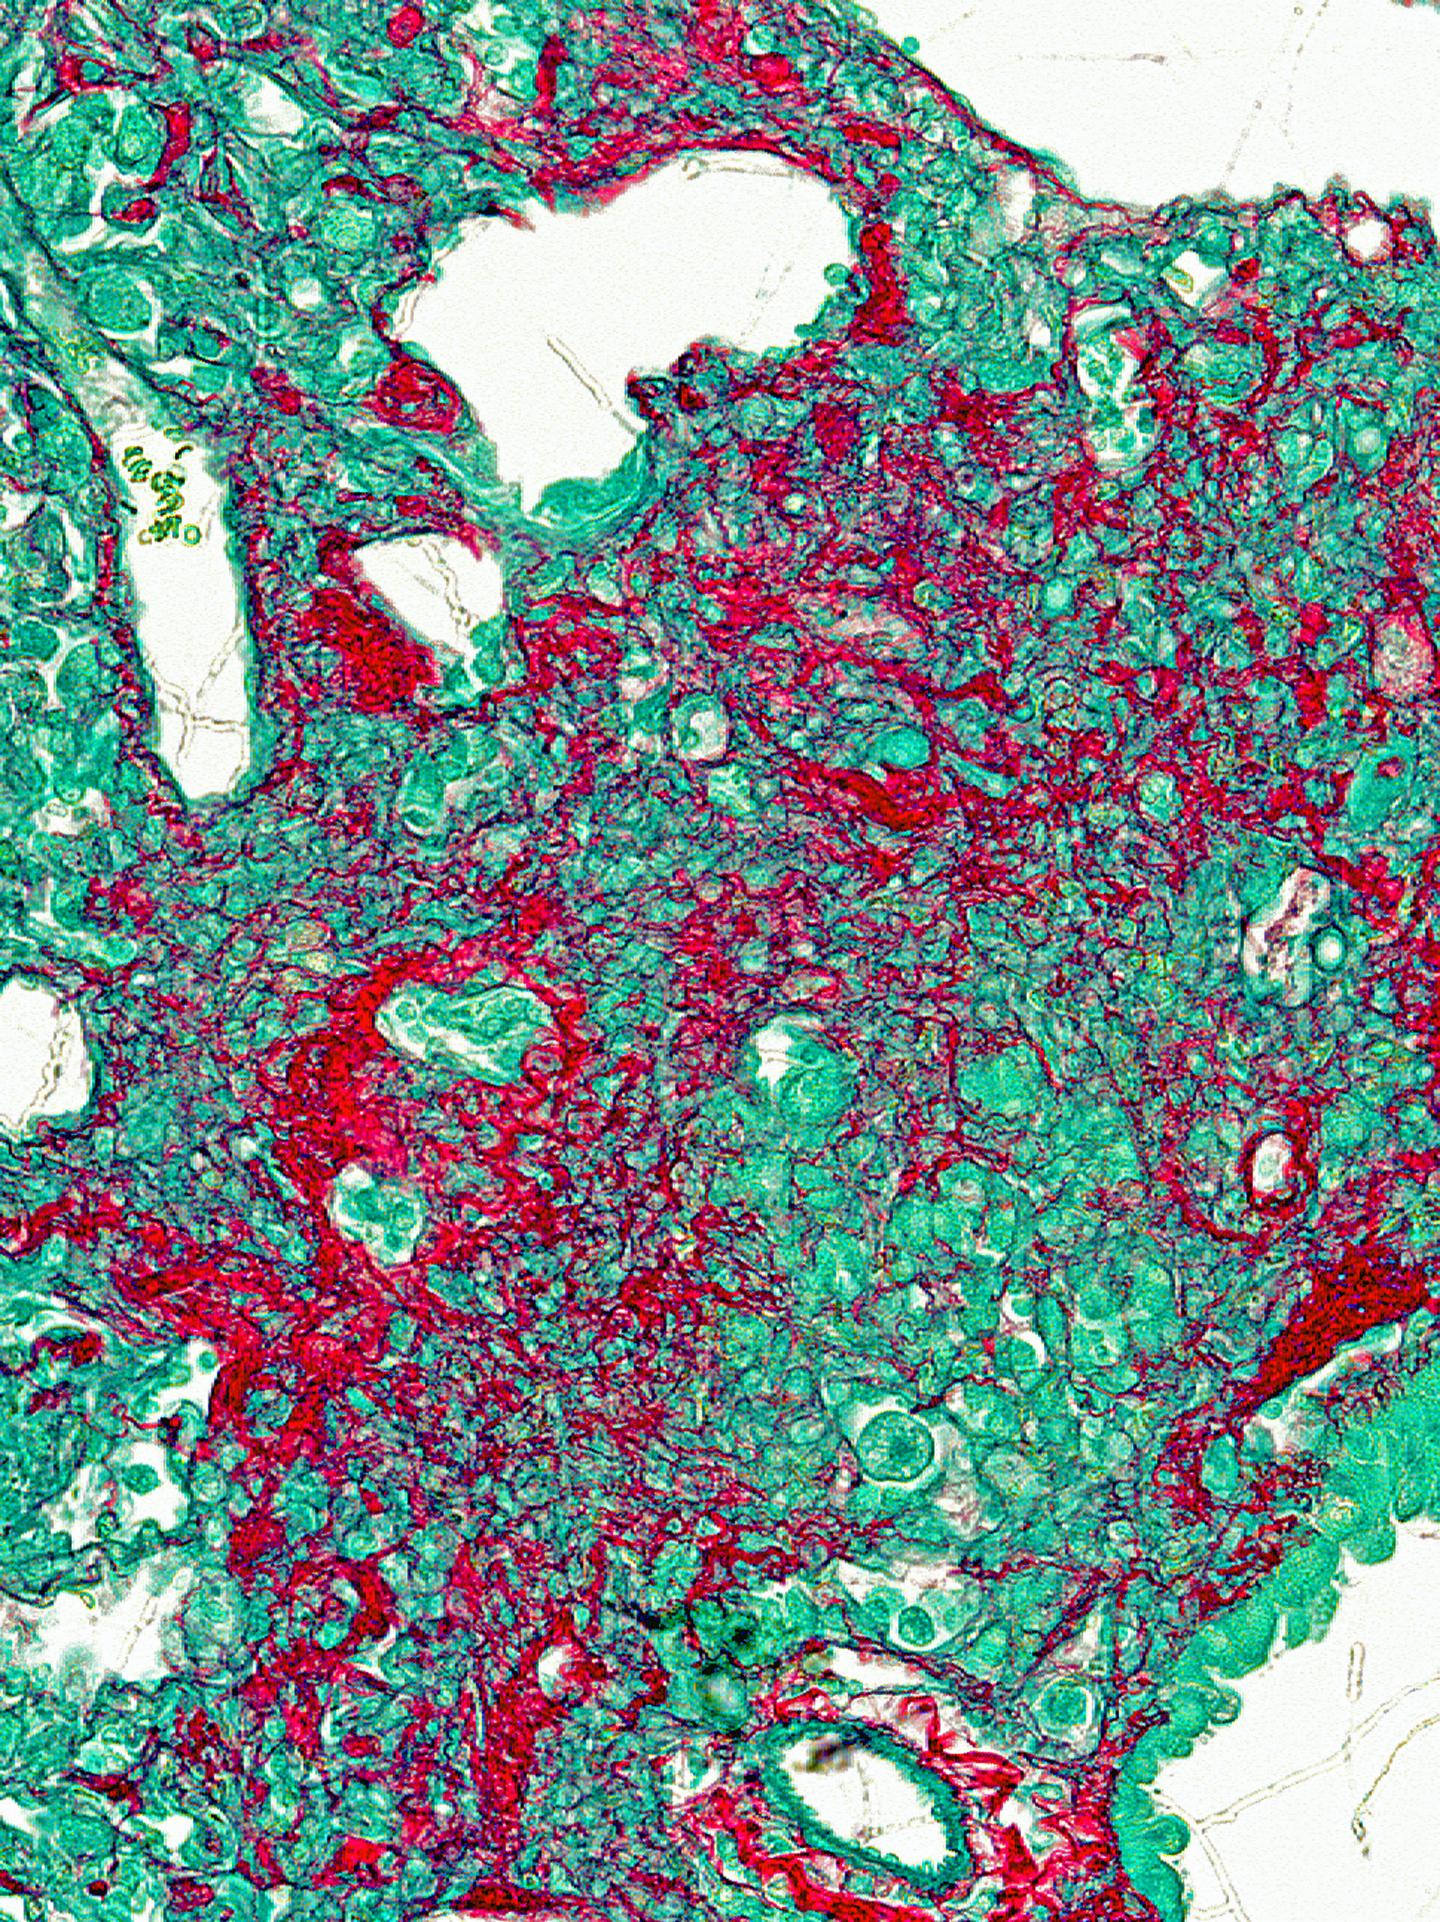

A research team at Cincinnati Children's Hospital Medical Center reports its data in the journal Cell Reports . It found that a gene called FOXF1 inhibits the IPF disease process, which includes extensive scarring in lung connective tissues, hyper-production of harmful cells called myofibroblasts and excessive lung inflammation.

Their data show human lungs from IPF patients and mouse models of IPF lack FOXF1 in myofibroblasts. But cells lacking FOXF1 also exhibit overexpression of a related gene called FOXM1, which drives lung scarring and inflammation.

FOXF1 induces CDH2, but inhibits CDH11 to shut down IPF if something triggers it. Researchers performed extensive lab and genetic analyses on biopsied human lungs donated by IPF patients and mouse models of IPF to find out that when FOXF1 is repressed its sister gene FOXM1 increases and fuels the disease.

To induce and study the IPF disease process in laboratory mice, the rodents were administered a chemotherapy agent for treating certain cancers called bleomycin. The chemical is toxic to the respiratory system and triggered tissue damage and fibrotic scarring in the animals' lungs. Human IPF biopsy samples were also used in these studies.